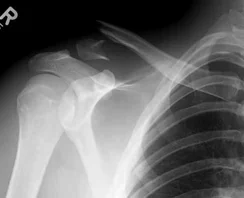

Clavicle Fracture

- Sites:

- Lateral thirds,

- Middle thirds, common (why?)

- Medial thirds

Its weakest point. The lateral fragment is depressed by the weight of the arm against trapezius, thus the shoulder droops, it is pulled medially forward by adductor function of pectoralis major causing the bone fragments to override.